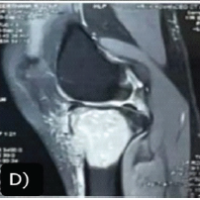

On post-operative day 2, a first wound inspection was performed with the removal of the drain. Multiple hemorrhagic blisters overlying erythematous skin, located adjacent to the surgical incision, were found over the left leg. Two to three clear, fluid-filled blisters overlying erythematous skin were found over the right leg (Fig. 3). Post-operative X-rays revealed a well-sited implant with no evidence of peri-implant fractures (Fig. 2). Distal pulses were intact postoperatively. Ultrasound venous Doppler images of both lower limbs showed no evidence of deep vein thrombosis. Biochemical markers of infection (C-reactive protein, TWC??) were unremarkable. What were the hemoglobin and platelet levels, and were any coagulation studies performed? Collagen dressings were applied over the blister site. Two to three large blisters were deroofed. Loose non-adherent dressings were done on both legs. Prophylactic intravenous cefuroxime 1.5 g was initiated and continued for 10 days to prevent infection. No further antibiotics were prescribed beyond this. Knee range of motion (ROM) exercises were initiated as tolerated by the patient. Full weight bearing was initiated on the 2nd post-operative day.

The limb edema started to subside by the 5th post-operative day, and the blisters started to epithelialize by the 7th post-operative day (Fig. 4). Suture removal was delayed up to the 16th post-operative day. The blistering eventually settled by 3 weeks duration without any evidence of deep infection (Fig. 5). On discharge, the patient had 90° flexion in both knees. One year follow-up showed good ROM (0 to 115 degree) an Oxford Knee Score of 46 value, which was acceptable, and no skin lesions.